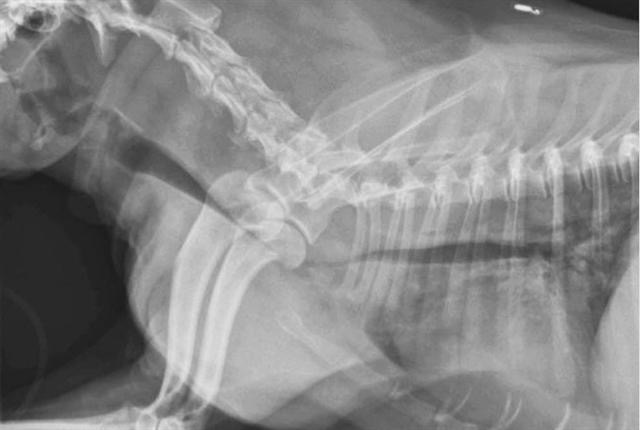

- Collapsus trachéal

- Flaccidité trachéale sévère

- Réalisation de vues radiologiques en inspiration et expiration